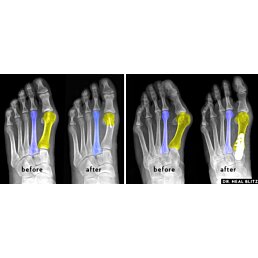

Hallux valgus (vbočený palec) je jednou z nejčastějších deformací chodidla, která způsobuje vychýlení palce směrem k ostatním prstům. Tento problém vede nejen k estetickým nepříjemnostem, ale i k bolestem, podráždění kůže a vzniku otlaku.